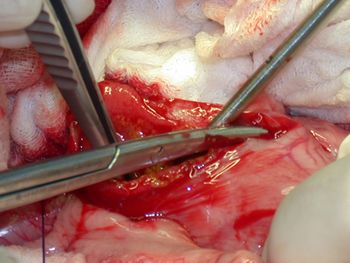

Dr. Steven Swaim demonstrates the best technique for creating these grafts to help close wounds in which local tissue is not available for closure.

A step-by-step guide to this simple way to repair wounds in which local tissue is not available for closure.